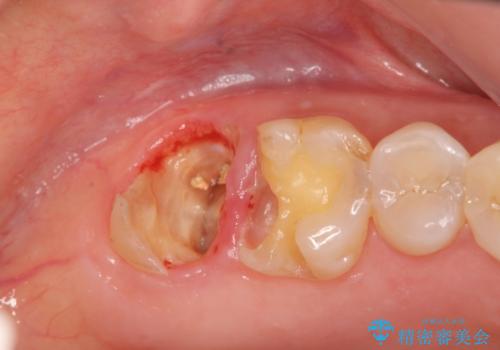

#17は失活歯で歯肉方向への縁下カリエス、#16は生活歯であるものの歯髄ギリギリの処置となるであろうとが予想される治療です。

歯周外科、マイクロスコープを用いた虫歯治療を行い歯を残す治療計画を立てます。

深い虫歯には歯周外科、マイクロスコープを用いた丁寧な虫歯の除去を行うことで歯の神経や歯そのものを残すことが可能になります。